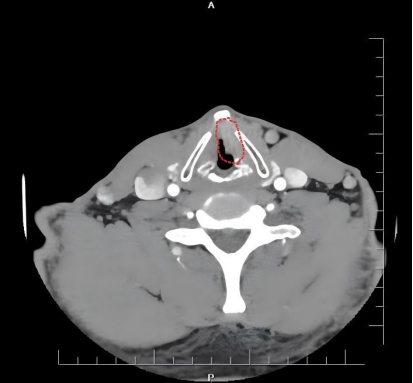

CT检查,红圈位置为病变部位

喉镜检查提示:左侧声带异常新生物,形态高度疑似恶性肿瘤。后续病理活检证实为鳞状细胞癌,病变范围较大,累及甲状软骨内膜,属喉恶性肿瘤中晚期。所幸目前未发现明确转移迹象,最终确诊为喉恶性肿瘤(声门型,鳞状细胞癌,T3N0M0,III期)。